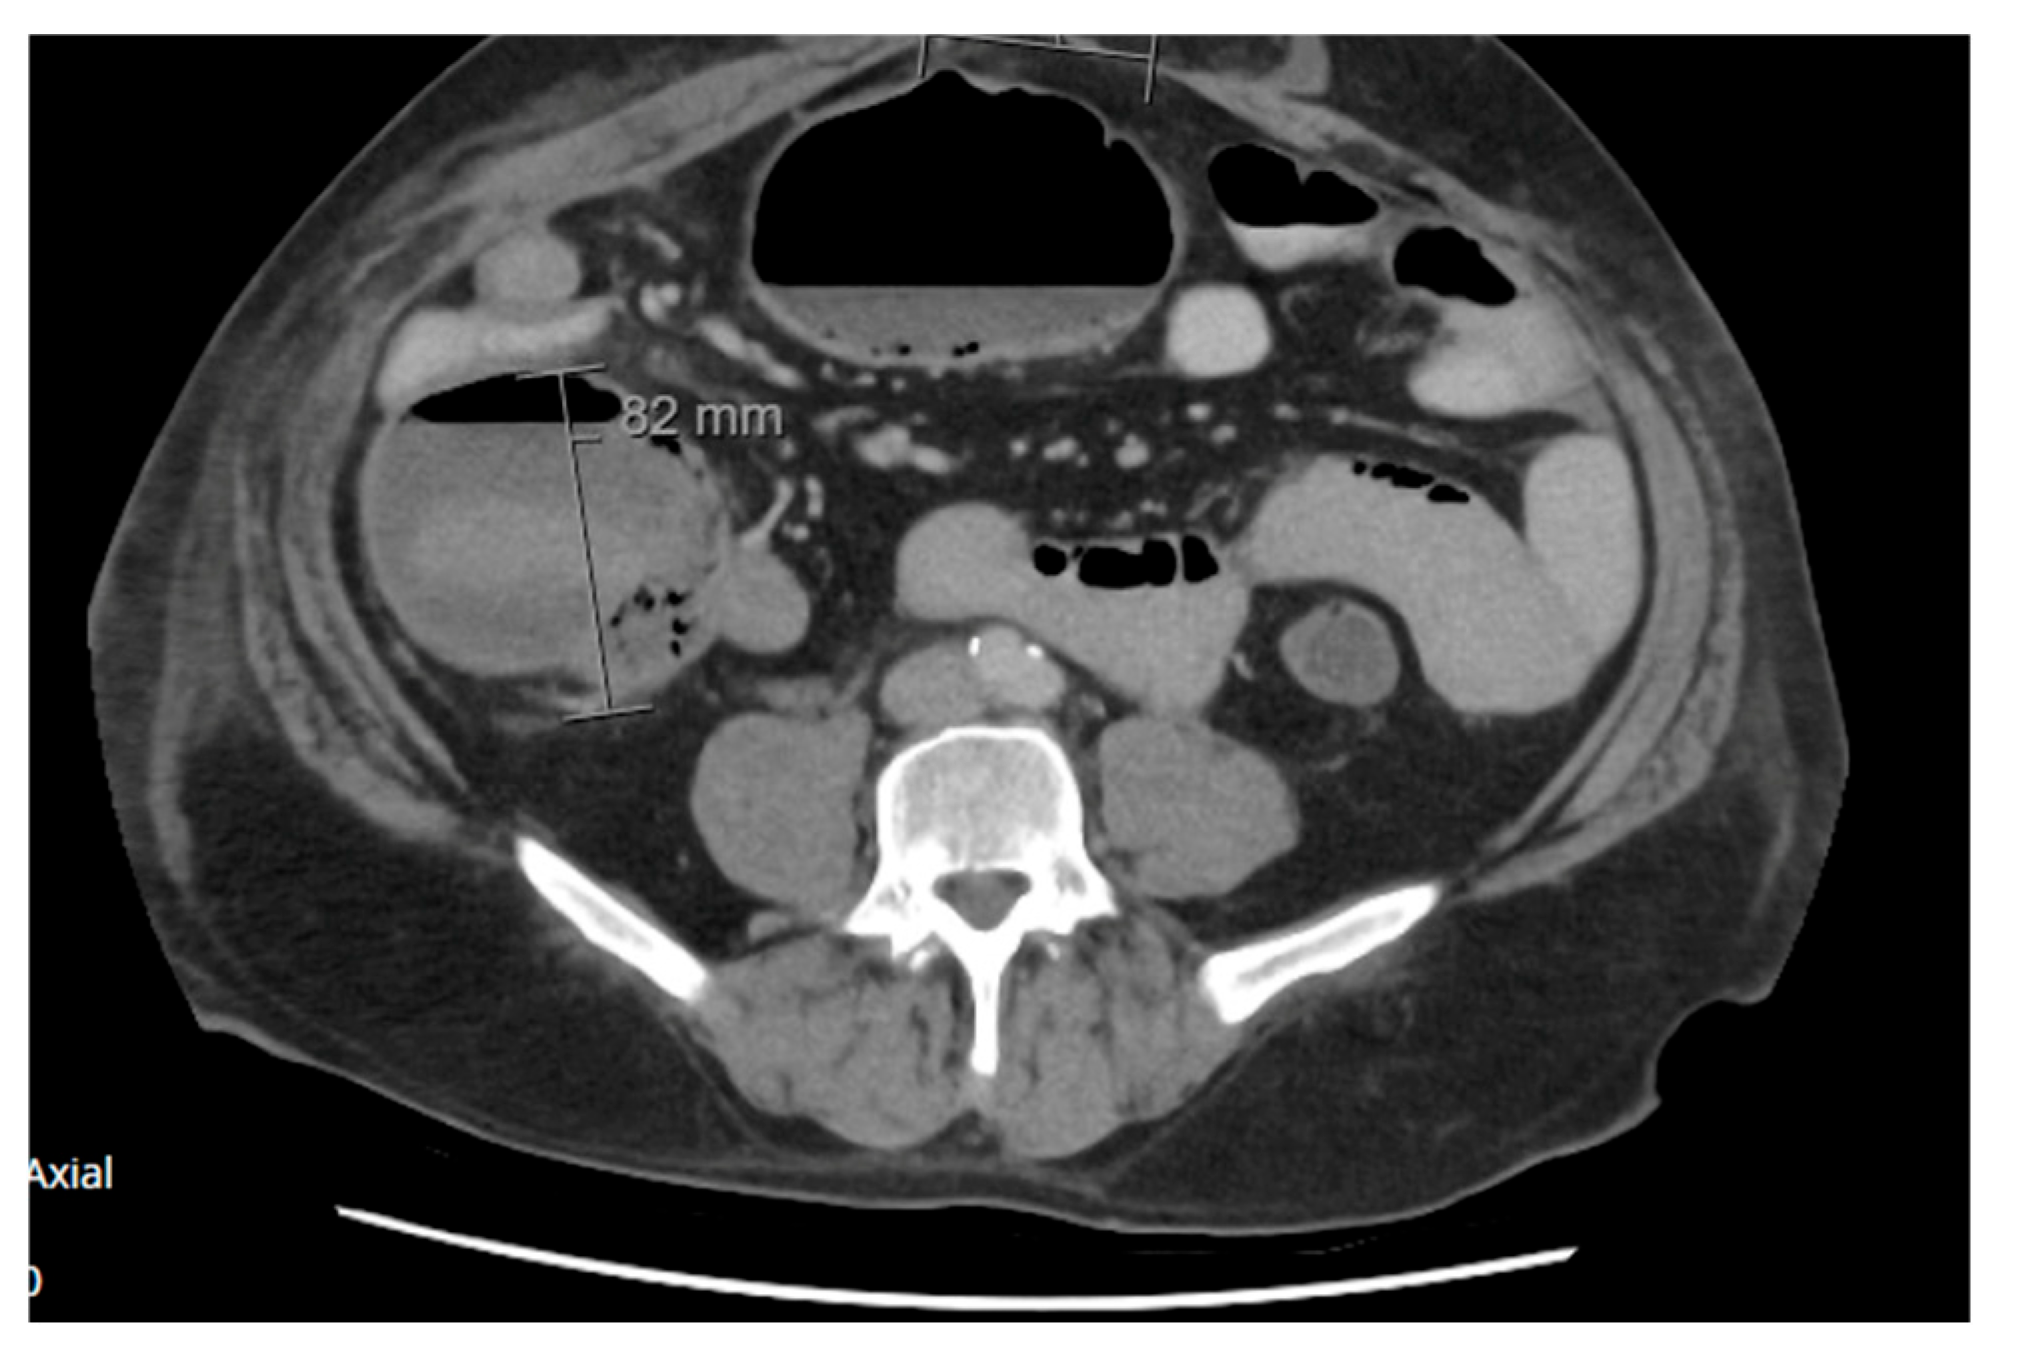

2.1.1. Case 1

2.1.2. Case 2